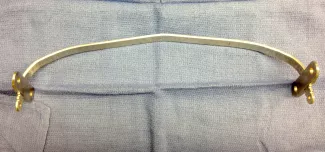

Open repair, called the Ravitch procedure, is done through a horizontal incision across the mid chest. In this repair the abnormal costal cartilages are removed, preserving the lining of cartilage, thus allowing the sternum to move forward in a more normal position. This procedure takes approximately 4–6 hours. In certain patients, an osteotomy (a break) in the sternum is done to allow the sternum to be positioned forward. In addition, to keep the sternum elevated in the desired position after the removal of the cartilages and the osteotomy, a temporary metal chest strut (bar) may need to be placed.

Repair with a metal pectus bar, called the Nuss Procedure, is achieved by bending a stainless bar to fit the chest wall. The bar is then inserted and secured through a small incision under each arm using the aid of a endoscope to monitor and avoid injury to the heart during insertion. The bar goes over the ribs and under the sternum, to push the sternum forward into the new position. The ends of the bar are secured to the chest wall. This procedure takes between 1–2 hours.

Patients who have a Ravitch procedure without a chest strut are seen only as needed after the first postoperative appointment. Ravitch procedure patients with a chest strut or Nuss procedure patients with a bar are seen at least annually after the first visit. The strut or bar is expected to stay in place for 2-3 years.